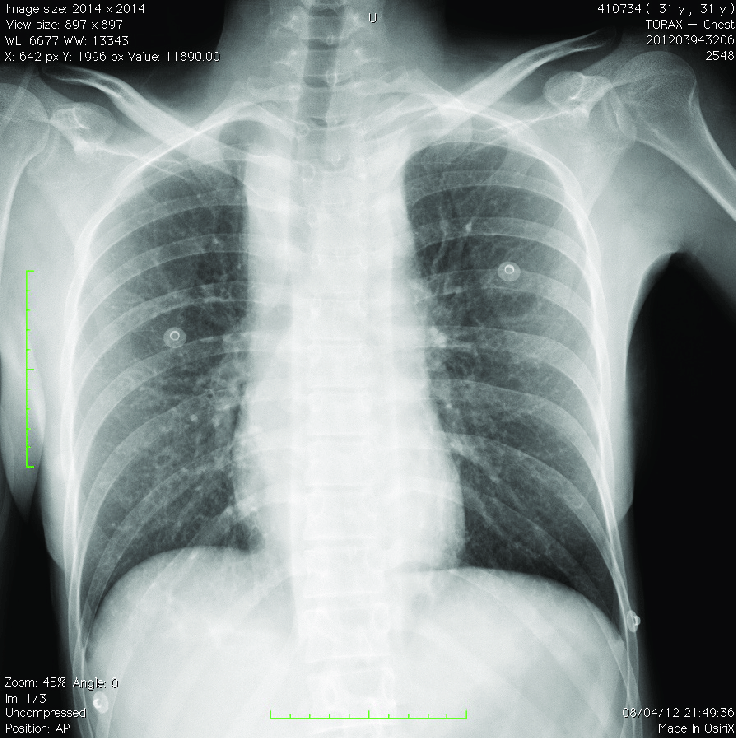

CIR - diagnóstico, clínica e conduta?

contusão pulmonar

murmúrio reduzido em um dos sítios sem alteração na saturação e na fc

conservador: o2 e fisioterapia, ventilação mecânica se hipoxemia importante